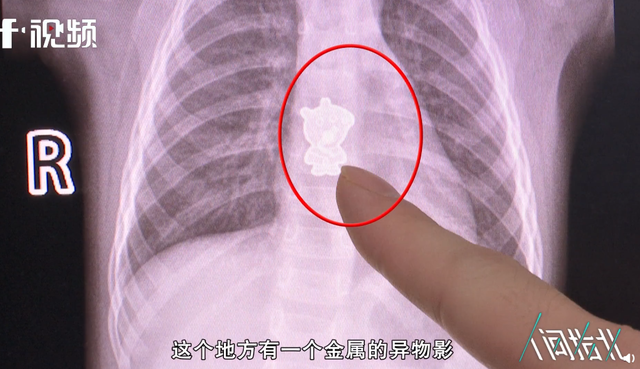

中國女童起床後哭鬧不休 就醫檢查喉嚨卡「佩佩豬」